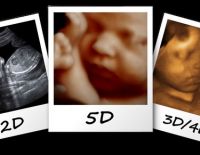

Siêu âm 5D những thông tin đầy đủ – hữu ích và cần thiết

Siêu âm 5D là một trong những hình thức siêu âm mà các mẹ bầu sẽ thực hiện trong quá trình thai kỳ. Tuy nhiên, nhiều chị em còn băn khoăn chưa hiểu rõ về hình thức siêu âm này ra sao? Vậy, bài chia...

Thai 21 tuần siêu âm 4D có nên hay không mẹ nên biết

Thai 21 tuần siêu âm 4D có nên hay không là điều mà nhiều mẹ bầu thắc mắc trước khi thực hiện thủ thuật siêu âm hiện đại này. Nếu đây cũng là thắc mắc của bạn thì hãy cùng lắng nghe ý kiến của...